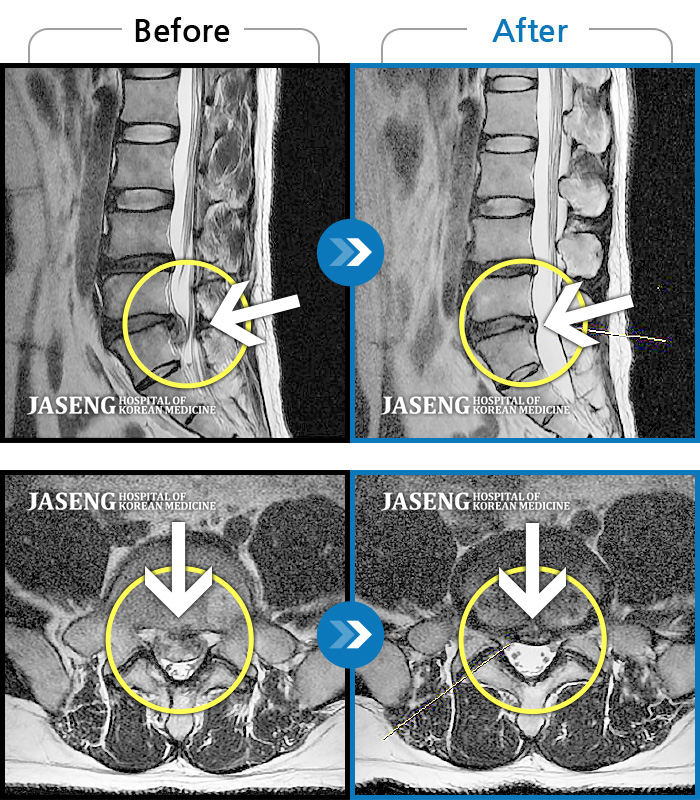

MRI 치료사례

처음 내원 시 허리통증과 왼쪽 다리 저림, 당김, 터질 듯한 통증으로 보행이 어려울 정도로 힘든 상태였습니다.